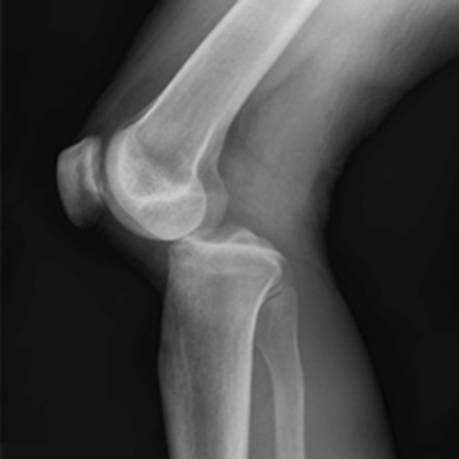

С вывихом колена пострадавшие редко обращаются в травматологию. Этот сустав крупный, подвижный, оснащенный мощным связочно-сухожильным аппаратом. Чтобы формирующие его кости сместились относительно друг друга, на сустав должно быть оказано сильное механическое воздействие. Поэтому вывих колена диагностируется у профессиональных спортсменов, людей, упавших с большой высоты или пострадавших в дорожно-транспортных происшествиях.